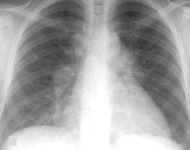

CXR showing changes consistent with simple silicosis or coal workers' pneumoconiosis

From the personal collection of Kenneth D. Rosenman, Michigan State University